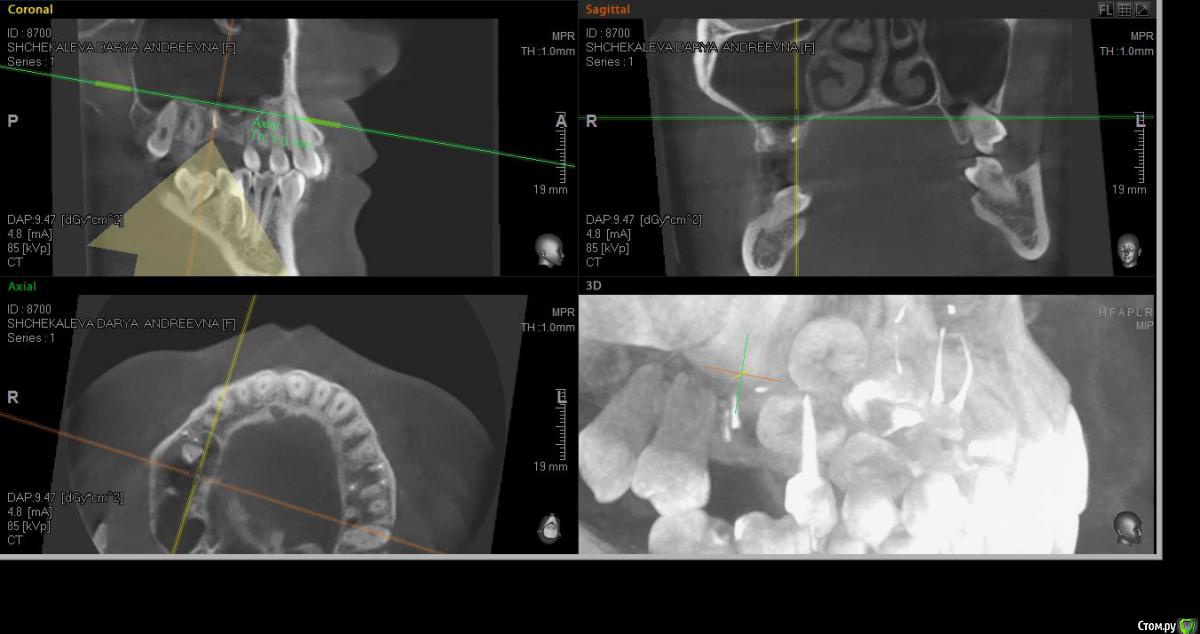

alekszander Опубликовано 14 марта, 2016 Поделиться Опубликовано 14 марта, 2016 Собственно вопрос кто сам доставал какие особенности? Или все же лучше к ЛОРу через эндоскоп?Боюсь только что корень с мембраной создал спайку и во время удаления просто порву мембрану.Дальние корни попробую аккуратно периотомом убрать. Ссылка на комментарий

faity Опубликовано 14 марта, 2016 Поделиться Опубликовано 14 марта, 2016 Можно со стороны альеолярки влезть, можно сразу окно выпилить.Для начала делаете доступ для визуализации, визуализируете апекс, потом аккуратно цепляете апикально чтобы мембрану не порвать, подойдёт кюретажка Лукаса маленькая 2мм и как с кистой или грануляцией вылущиваете. Если протолкнули- снимок и окно в проекции. 1 Ссылка на комментарий

alekszander Опубликовано 14 марта, 2016 Автор Поделиться Опубликовано 14 марта, 2016 Если протолкнули- снимок и окно в проекции.Что имеете ввиду если протолкнул, при попытке достать корень толкнул его глубже? И не совсем понял про снимок, помню читал тему, что его подшивают, но не совсем понял как в в данном случае - уложить и потом отдельно доставать? Ссылка на комментарий

Глеб Митрофанов Опубликовано 15 марта, 2016 Поделиться Опубликовано 15 марта, 2016 3 Ссылка на комментарий